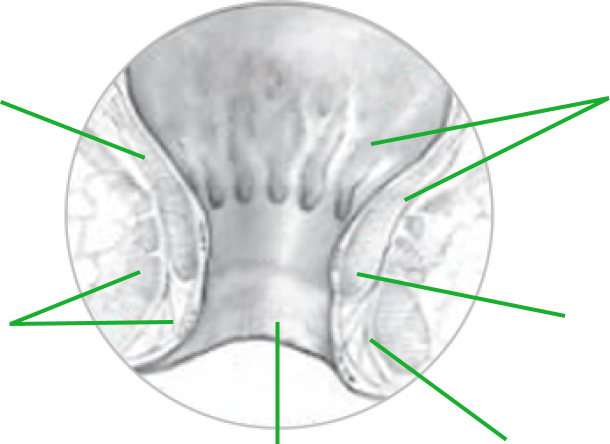

ZDROWA ODBYTNICA

Ścianka mieśniowa

Mięsień zwieracza zewnętrznego

Błona śluzowa

Mięsień zwieracza wewnętrznego

Kanał odbytu

Skóra